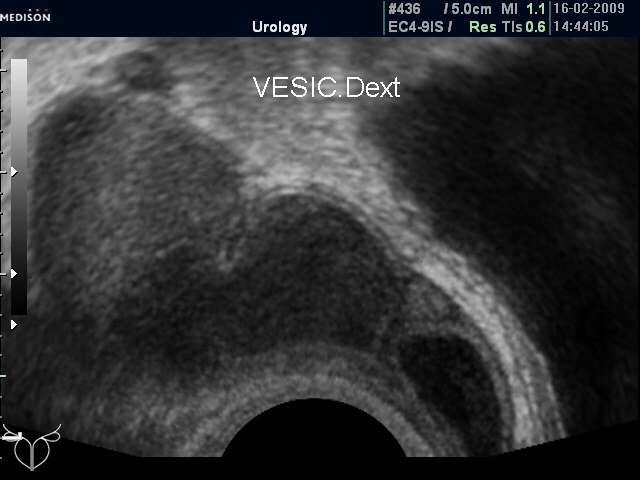

Досылаю фото семенных пузырьков.

Кистозная трансформация семенного пузырька